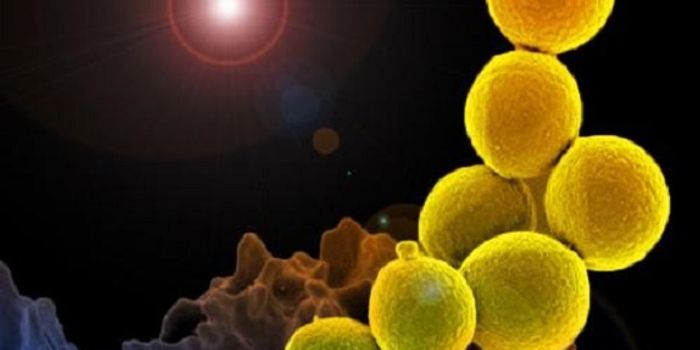

JUN 08, 2018MicrobiologyThe S. aureus pathogen doesn't only invade bone, it uses it as a snack.

AUG 20, 2016Clinical & Molecular DXCan the staph superbug, also known as MRSA, be brought down by salt? Scientists finally expose a key weakness in these b ...

MAR 11, 2015MicrobiologyHouseholds can serve as a reservoir for transmitting methicillin-resistant Staphylococcus aureus (MRSA), according to a ...